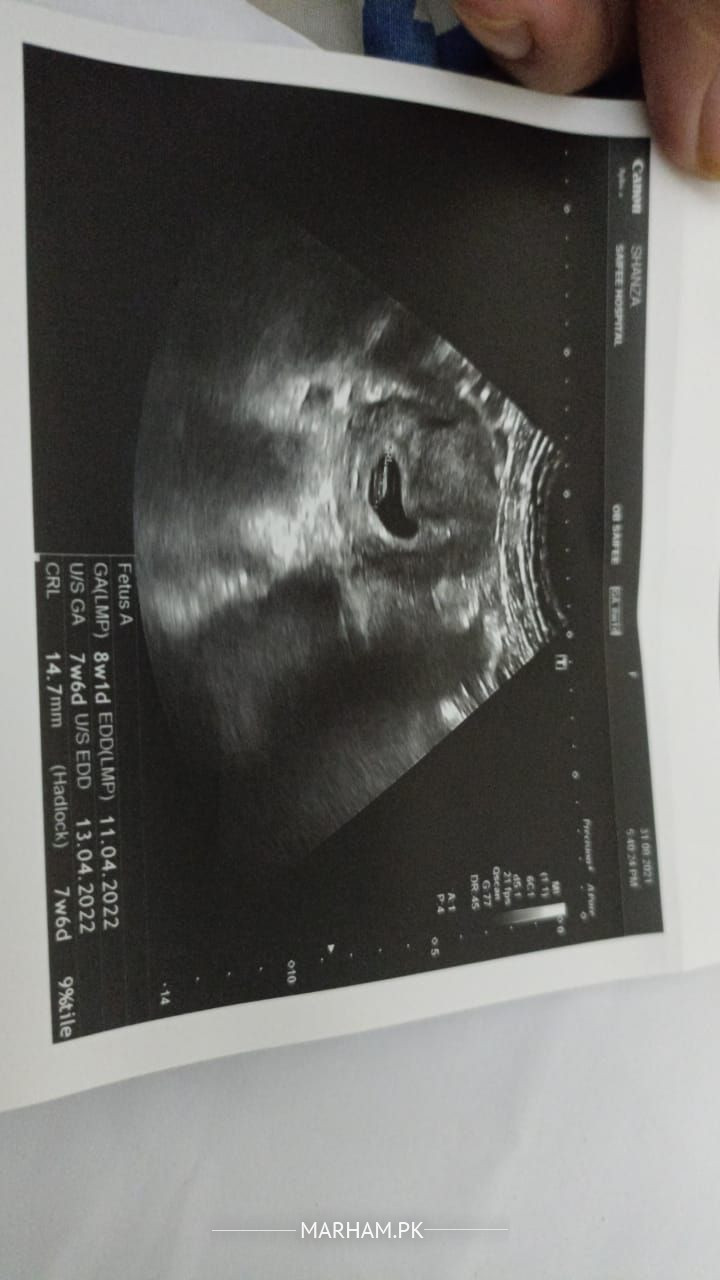

Asking For Self, Female 23, North Nazimabad

plz tell doctors plz guide me .. what's the problem .? cyst ha koi prob h. Kuch issue h. Kia krwana chaye . I'm two months pregnant .

ask sonologist for report

report is attached in this post

wait till ur pregnancy terminated